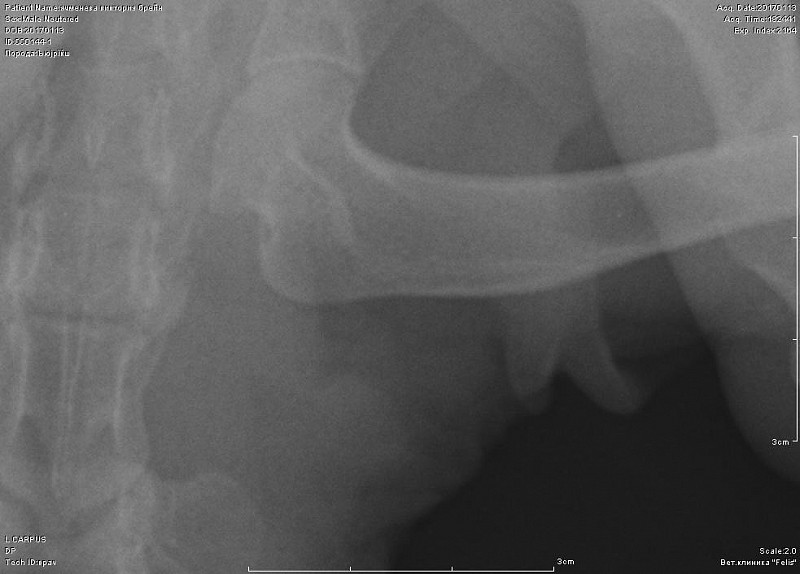

вот такой снимок целиком-первое фото-это я увеличила, может быть другие суставы на этой лапе Вы тоже посмотрите. А также, пожалуйста, порекомендуйте кому можно показать кота в спб, может Вы знаете.

Вот снимок, посмотрите, пожалуйста.

По-прежнему не вижу перелома, но последнее изображение увеличить не могу.

вот в запястном суставе не вижу изменений.А вот локтевом есть признаки артроза. Но все же это не прямая и даже не боковая проекция локтя.